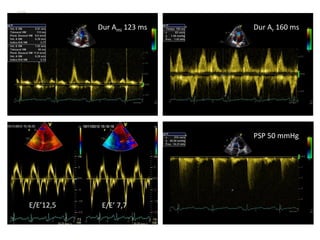

 19 años, trasplante hepático por atresia de vías biliares.

 Hiperactividad

 Tto. con tacrolimus.

 AF: madre F.A./flutter, coartación Ao, ICFEP; Hermana VAB, hepatitis

autoinmune.

 Disnea de esfuerzos moderados desde hace 1,5 meses.

Dur Ami 123 ms Dur Ar 160 ms

PSP 50 mmHg

E/E’12,5 E/E’ 7,7

 19 años,trasplante hepático por atresia de vías biliares.  Hiperactividad  Tto. con tacrolimus.  AF: madre F.A./flutter, coartación Ao, ICFEP; Hermana VAB, hepatitis autoinmune.  Disnea de esfuerzos moderados desde hace 1,5 meses.

Dur Ami 123ms Dur Ar 160 ms PSP 50 mmHg E/E’12,5 E/E’ 7,7